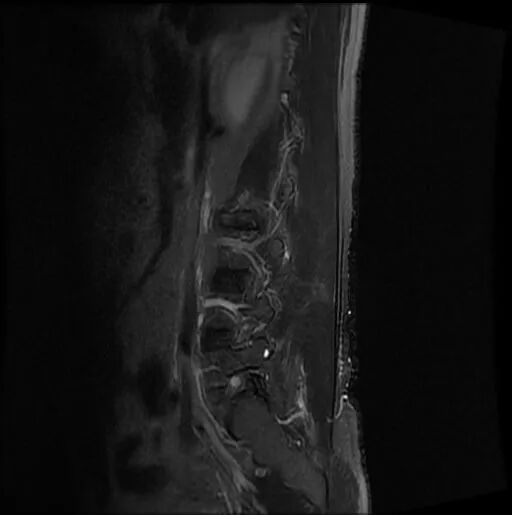

圖3:術(shù)前MRI

術(shù)前影像資料